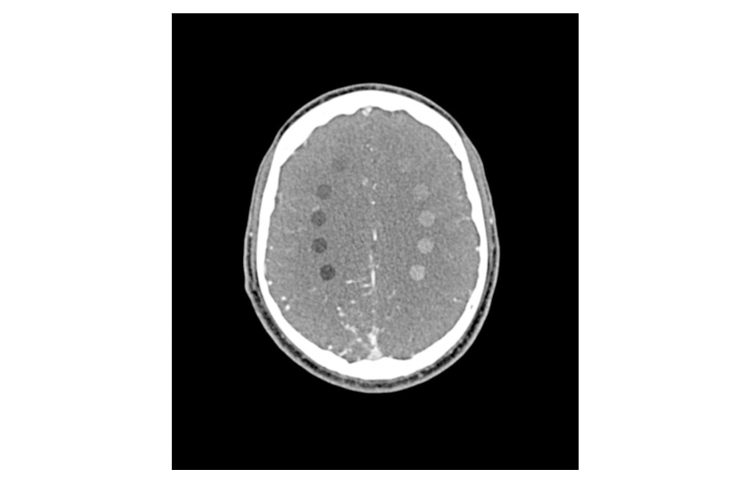

50-04頭部CTA AVM/病變模體模擬了在動(dòng)脈期增強(qiáng)的對(duì)比劑增強(qiáng)頭部(CT 血管造影)。它從頂點(diǎn)到枕骨大孔。模體在半卵圓中心有10個(gè)低對(duì)比度病灶,右半球有一個(gè)動(dòng)靜脈畸形。

每側(cè)半卵圓中心的室周和室上水平有5個(gè)棒狀病變。

病灶直徑:10毫米

病灶高度:10.5毫米

病變對(duì)比:在120 kVp時(shí)約-60至-20和20至60 HU